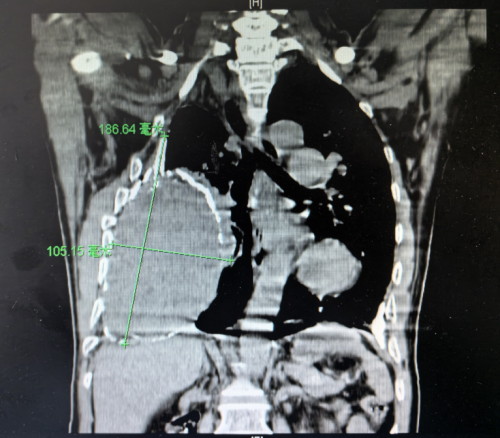

胸外科、心脏大血管外科,科室主任、主任医师袁跃西查看了张根水的胸部CT,清晰可见他的右侧胸腔存在一个巨大的慢性包裹性脓胸,因为病程长,病灶迁延不愈,包裹的纤维板已经钙化为一层厚厚的硬壳,脓腔里还有18×10cm机化的坏死组织,宛如一个“硬壳鸵鸟蛋”塞进了他的胸腔。

术前CT